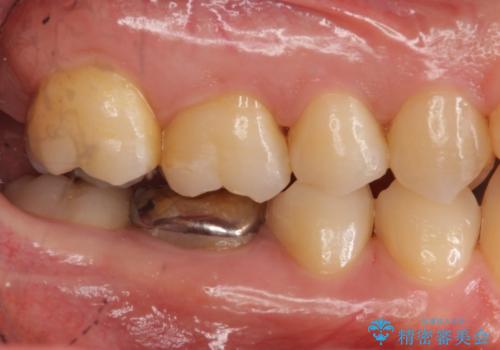

- 右下の奥歯に入れた銀歯を白くしたいとのことで来院されました。

根っこの治療がされていますが、症状もなくレントゲン画像で病変も確認できないため根管内には触れず被せ物のやり替えのみとなりました。

- 右下6 仮歯+セラミッククラウン 11000円+110000円費用は治療当時の料金となります